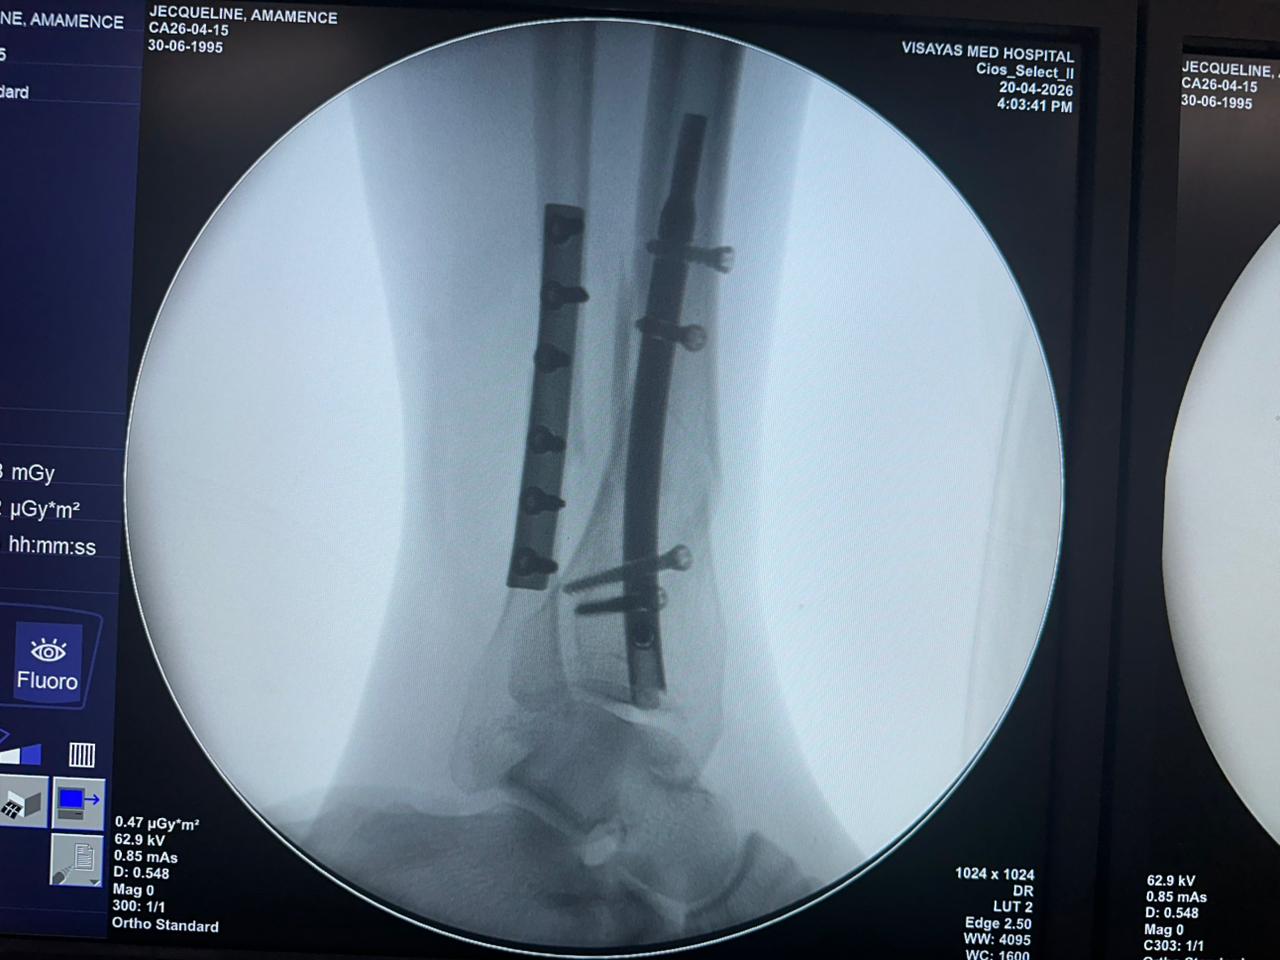

Étude de cas sur la fixation d'un clou tibial distal avec support de plaque fibulaire

Radioscopie peropératoire de l'arceau, vues AP et latérales

Ce cas concernait une fixation tibiale distale à l’aide d’un clou tibial distal intramédullaire. La radioscopie peropératoire a confirmé la position du clou, des vis de verrouillage distales et de la fixation par plaque fibulaire.